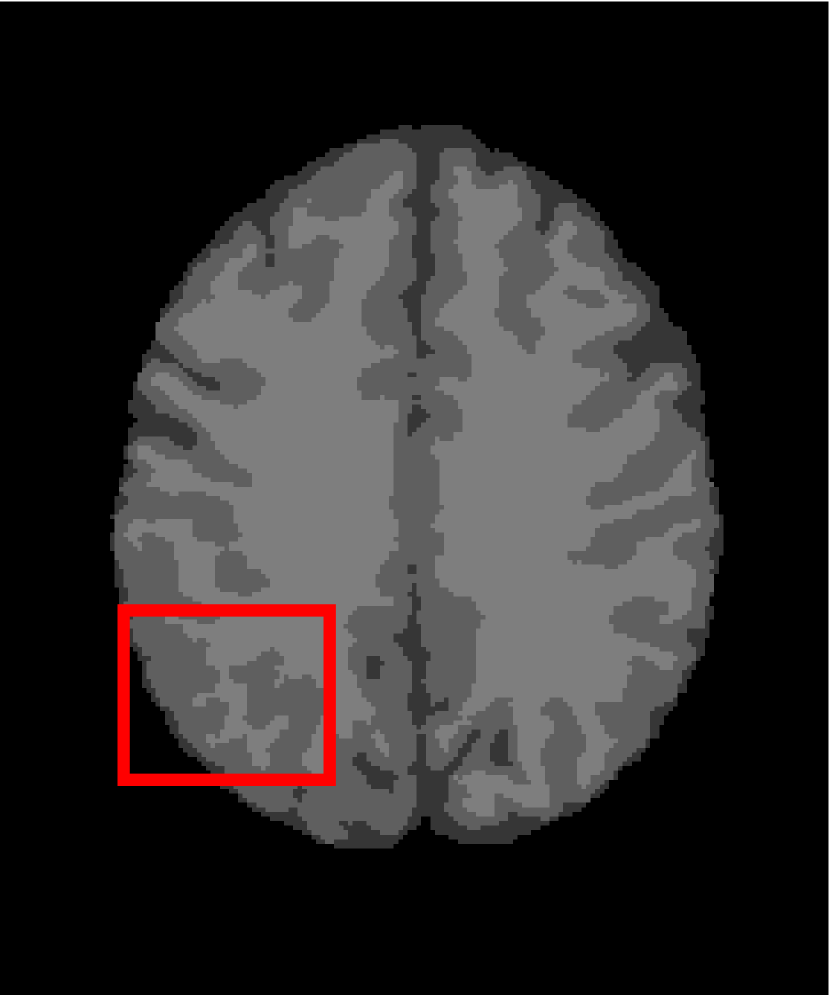

In the second experiments, we segment two medical images coming from a simulated brain database (BrianWeb): http://www.bic.mni.mcgill.ca/brainweb/. The two images are generated by T1 modality with slice thickness of 1mm resolution, 9% noise and 20% intensity non-uniformity. Here, the two images are represented two slices in the axial plane with the sequence of 100 and 110. Moreover, there are golden standard segmentations in the dataset. We set the numbers of clusters to 4. The visual comparisons are illustrated in Figs. 6 and 7.

Figure 7: Segmentation results for the second medical image. From (a) to (l): ground truth, noisy image and results of FCM_S1, FCM_S2, FGFCM, FLICM, KWFLICM, ARKFCM, FRFCM, WFCM, DSFCM_N, and LRFCM.

By focusing on the marked red square in Figs. 6 and 7, we easily find that FCM_S1, FCM_S2, FGFCM and ARKFCM are sensitive to noise. FLICM and KWFLICM are vulnerable to severe intensity inhomogeneity. FRFCM brings overly smooth results due to the use of gray level histograms. WFCM and DSFCM_N cause several contours to change. However, LRFCM acquires clear contours and suppresses noise adequately. Moreover, we find that the segmentation result of LRFCM is closer to ground truth.